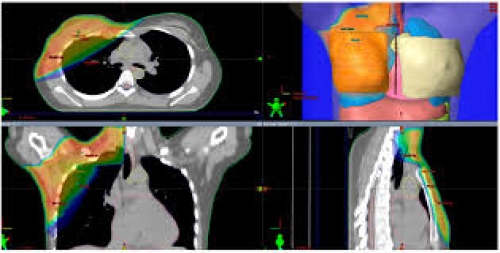

25 tháng 08, 2025Bài 3: Các kỹ thuật xạ trị hiện nay trong ung thư vú (3D-CRT, IMRT, Proton Therapy) Tìm hiểu chi tiết các kỹ thuật xạ trị ung thư vú: 3D-CRT, IMRT, proton therapy. So sánh ưu – nhược điểm, hiệu quả và lựa chọn ...Xem thêm